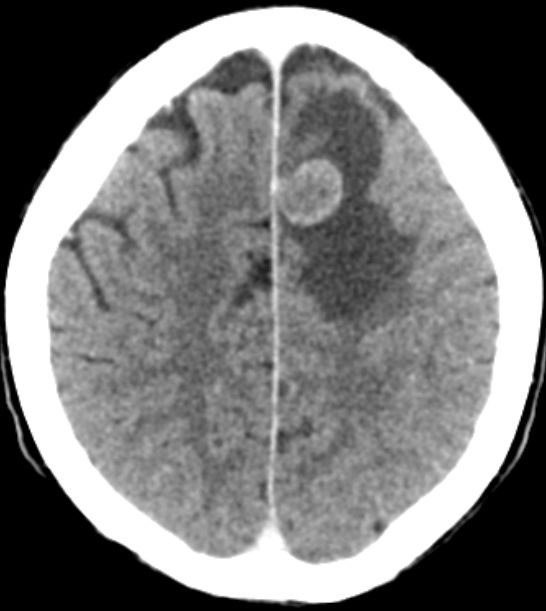

Hirnmetastasen CT nach KM-Gabe: Hirnmetastase